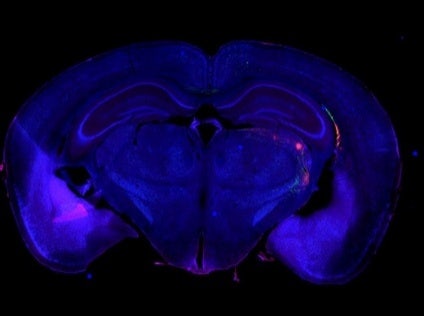

脳研究

AAV-GFPとAAVtdTomatoで標識された皮質視床投射路。

画像データ提供:Hong Wei Dong, MD, PhD, Professor of Neurology, Keck School of Medicine of University of Southern California.